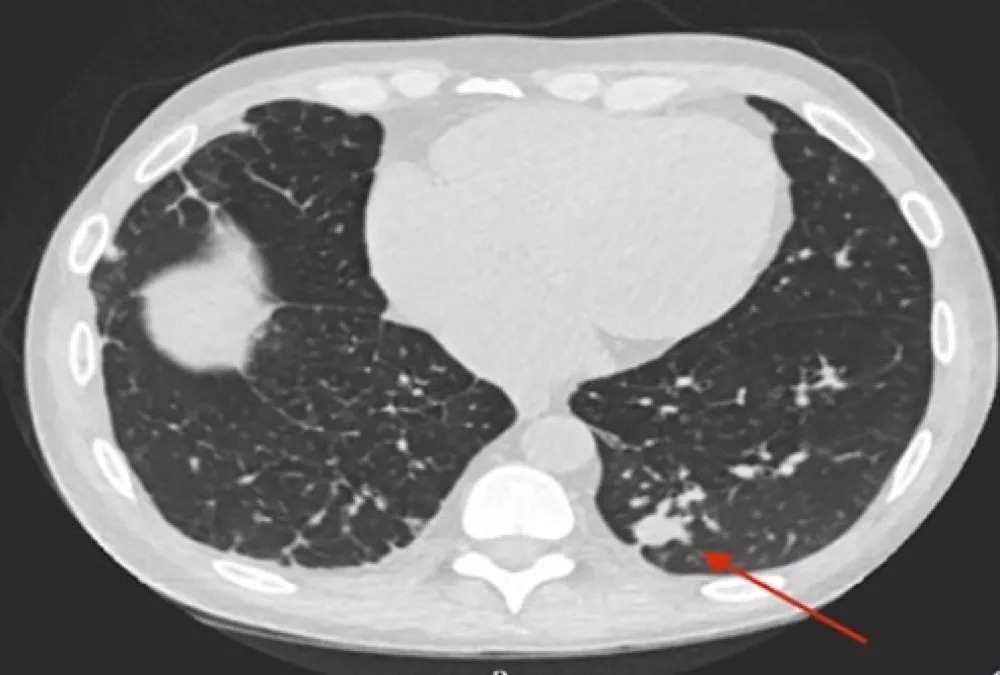

Febre, nódulo pulmonar e granuloma renal em um transplantado renal

Valkercyo Feitosa

3 anos atrás